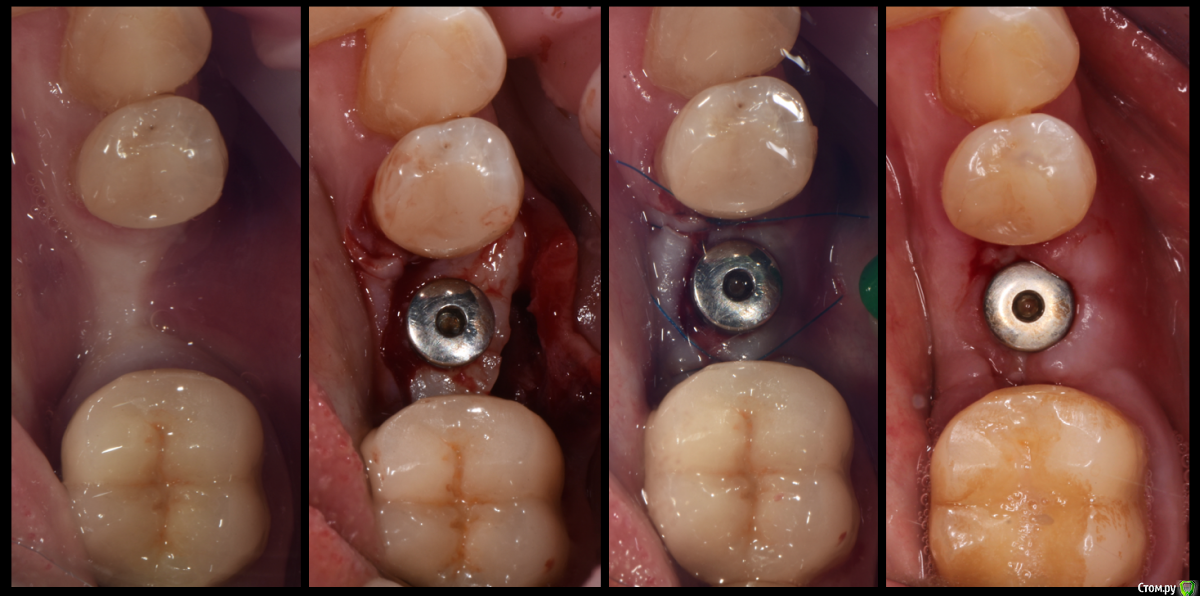

Проведена установка имплантата Impla 4,2*9,5 (отсутствует 35) в зоне выраженной атрофии мягких тканей. Торк получился около 45 Н/см. ССТ из зоны адентии в области отсутствующего 27 (бугра почти не было) взят в форме "бумеранга" для закрытия рецессии на 34.